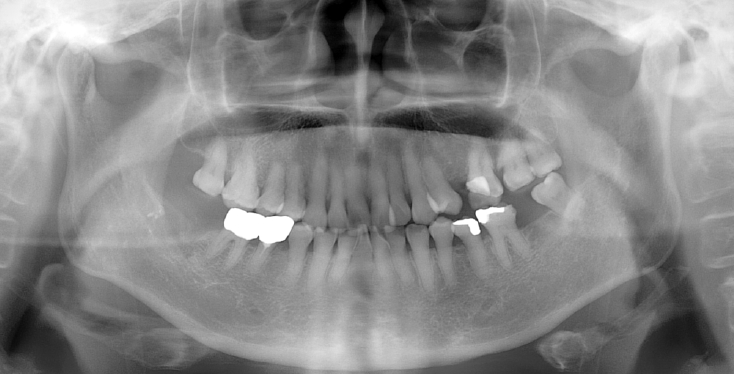

A 63-year-old female presented three days after endodontic treatment of the mandibular left second molar (#37) with symptoms of numbness in the left lower lip and gingiva. A panoramic radiograph and cone-beam computed tomography (CBCT) revealed extrusion of Calcipex II into the mandibular canal (Fig. 1). Initial neurosensory testing demonstrated mild hypoesthesia. She was admitted for foreign body removal and neurorrhaphy under general anesthesia. A post-operative panoramic radiograph confirmed the removal of the foreign body (Fig. 2). Although surgical curettage and neurorrhaphy were performed on the fourth day post-onset, no significant symptom relief was noted at the one- and two-week follow-ups. At the three-month follow-up, she reported persistent numbness with mild neuropathic discomfort but no marked improvement. A follow-up neurosensory exam is scheduled for the six-month check-up.